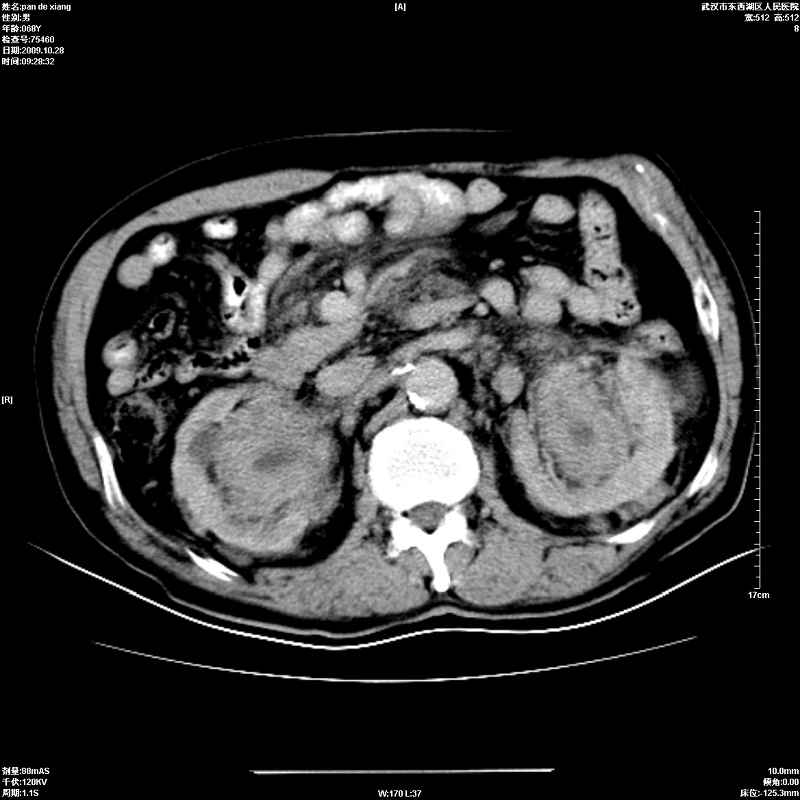

以下是引用杀毒软件在2009-10-28 20:41:00的发言:[br]结合临床考虑---白血病双肾改变或淋巴瘤。

以下是引用zxl51642在2009-10-29 9:59:00的发言:[br]结合临床“单克隆免疫球蛋白血症”,考虑双肾为继发损害并肾功能不全(尿中大量igg及少量iga、igm等大分子免疫球蛋白滤出所致继发损害),椎前软组织肿块为髓外造血。与浆细胞瘤有区别,平扫时有战友说的很清楚。